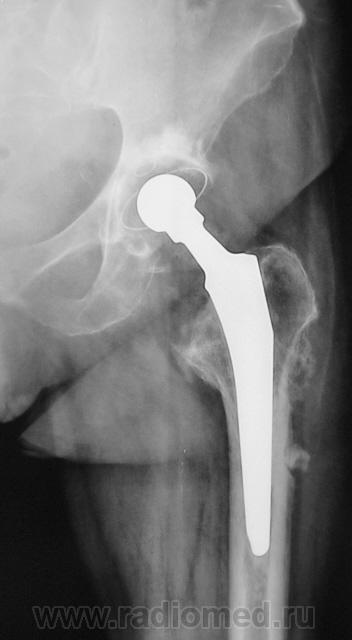

Шарнирный эндопротез. Пластиковая чашка установлена (по-моему правильно) в очищенной от суставного хряща вертлужной впадине и зафиксирована при помощи костного цемента. Ножка протеза в порядке. Какие-то остеофиты на латеральном контуре бедра (мелко: плохо видно).